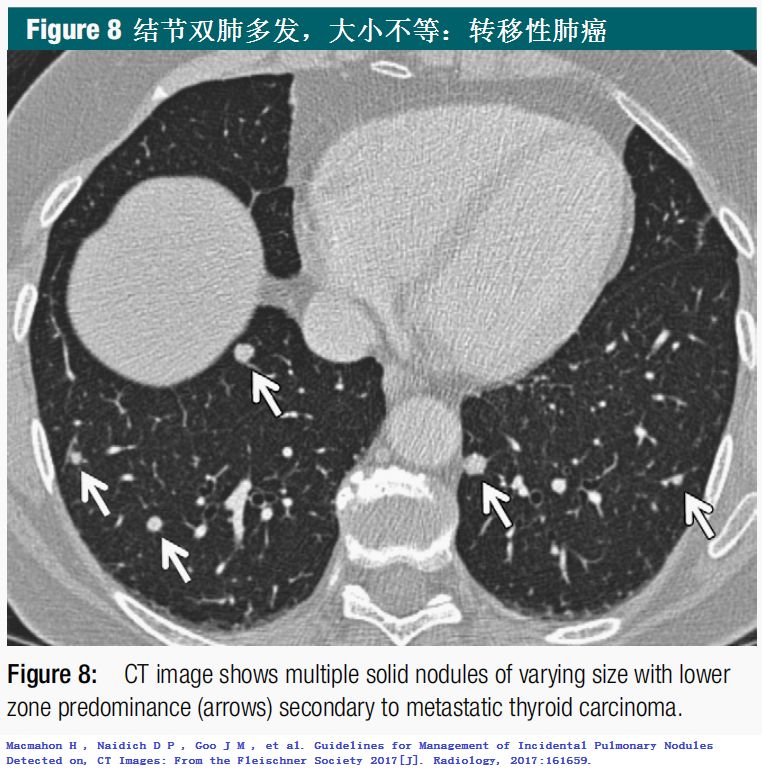

双肺多发结节,一头雾水,指南给你方向!

(图片点击均可放大)

2.Macmahon H , Naidich D P , Goo J M , et al. Guidelines for Management of Incidental Pulmonary Nodules Detected on, CT Images: From the Fleischner Society 2017[J]. Radiology, 2017:161659.